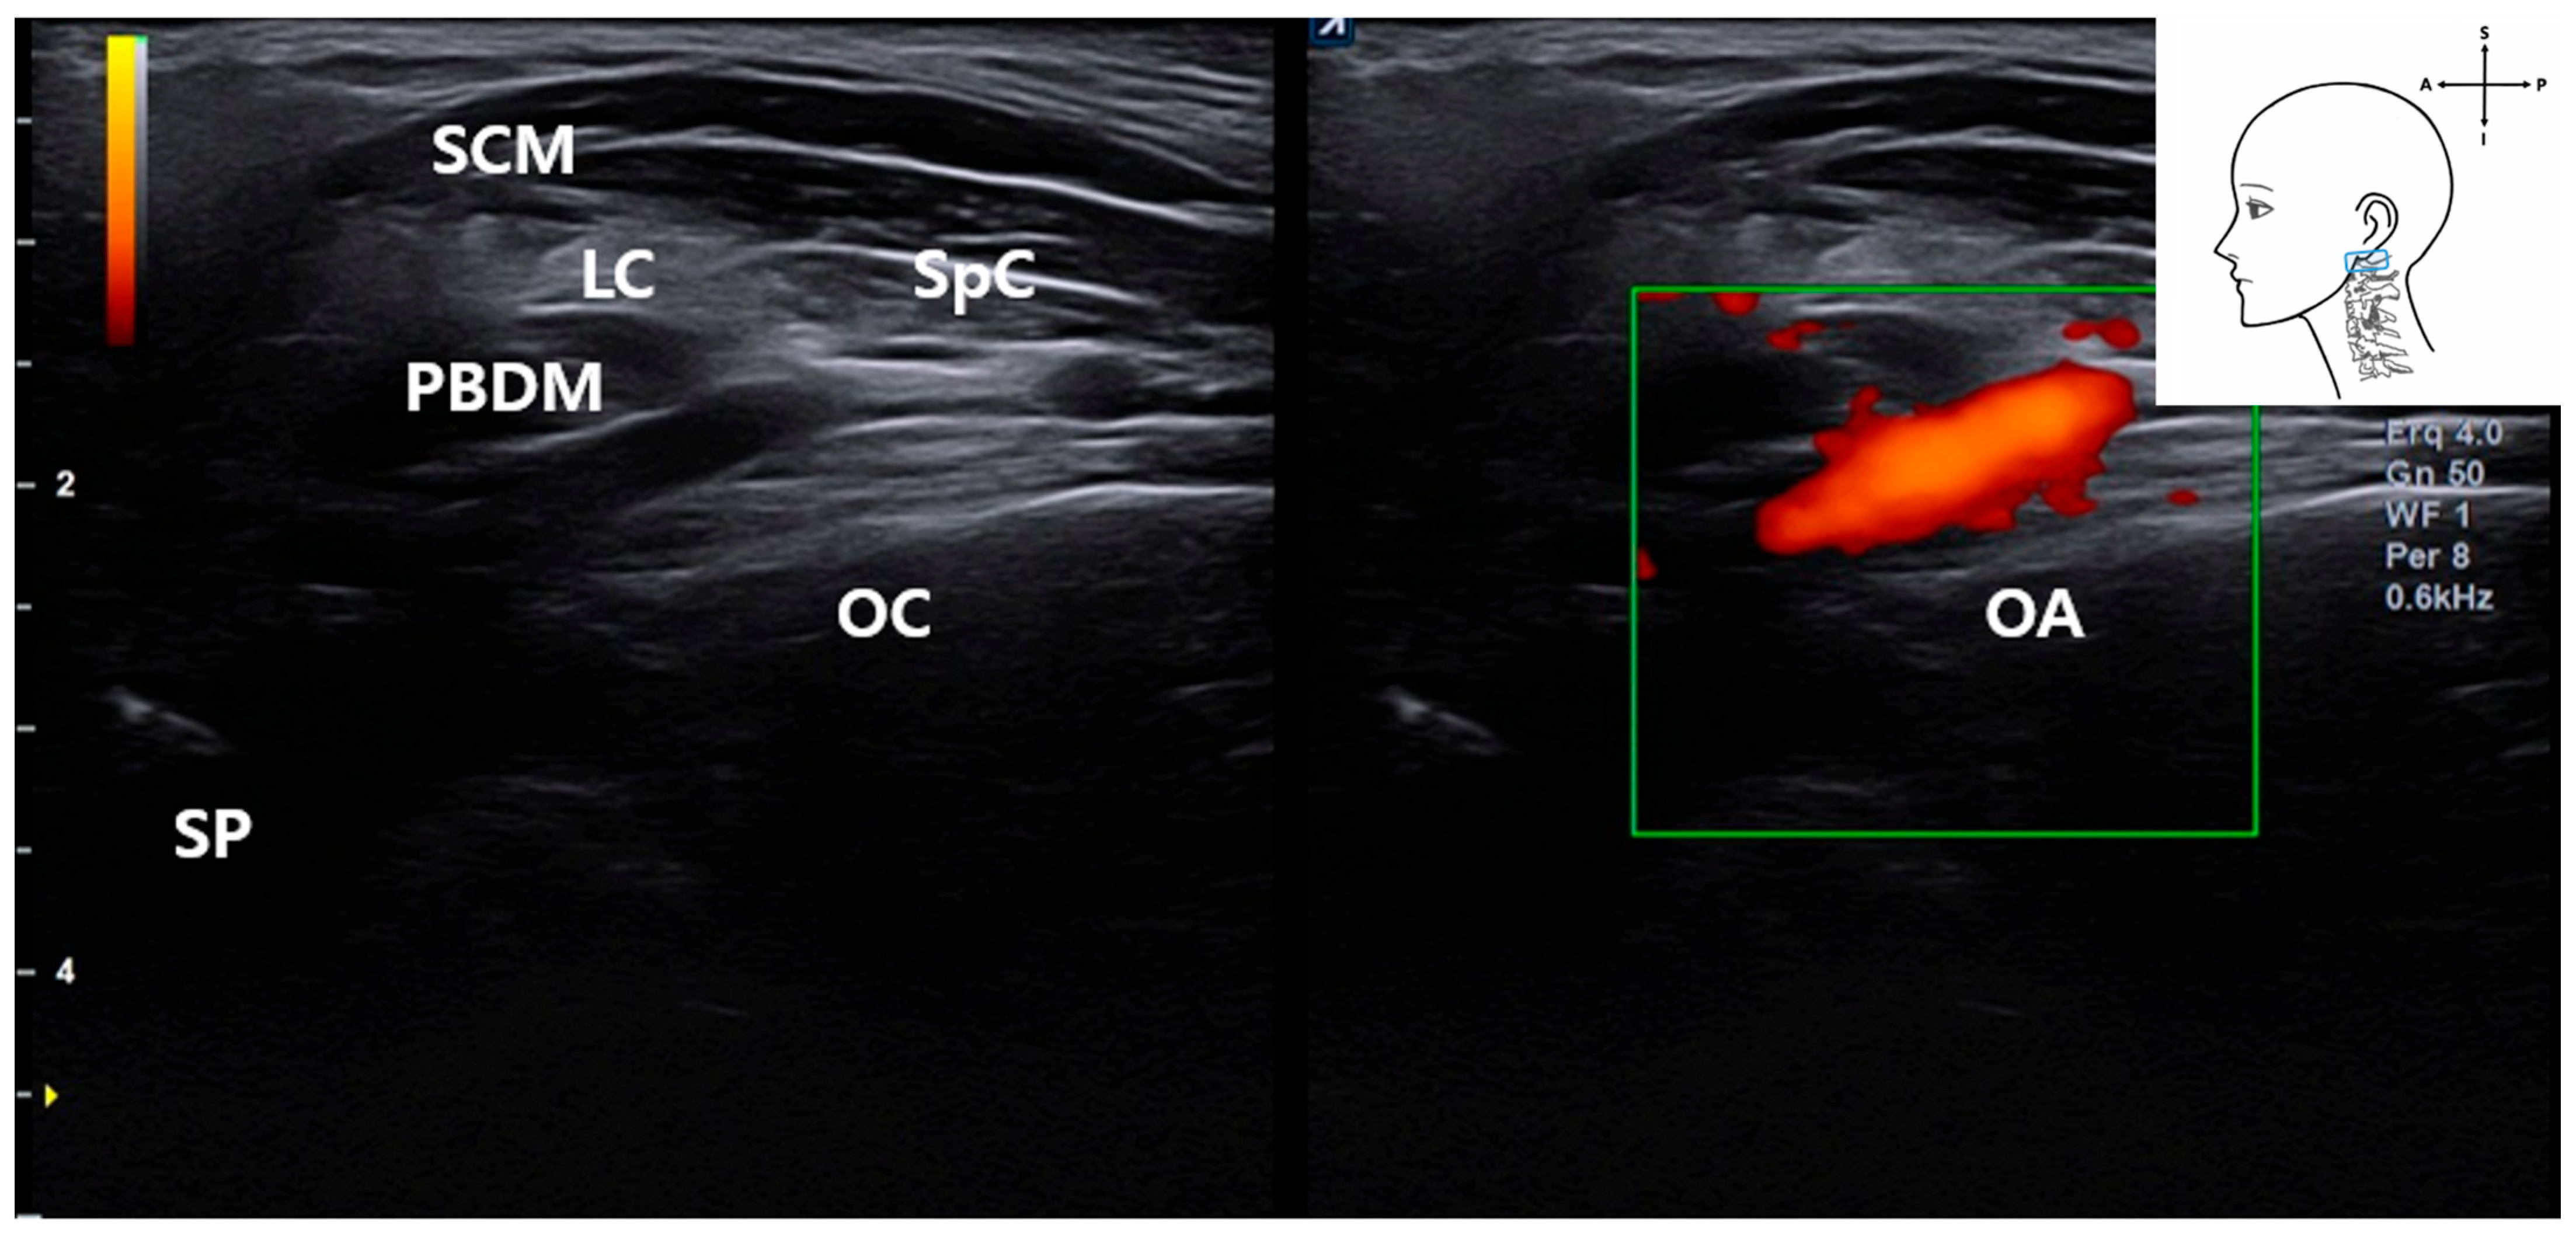

3.5. Identification of the Occipital Artery